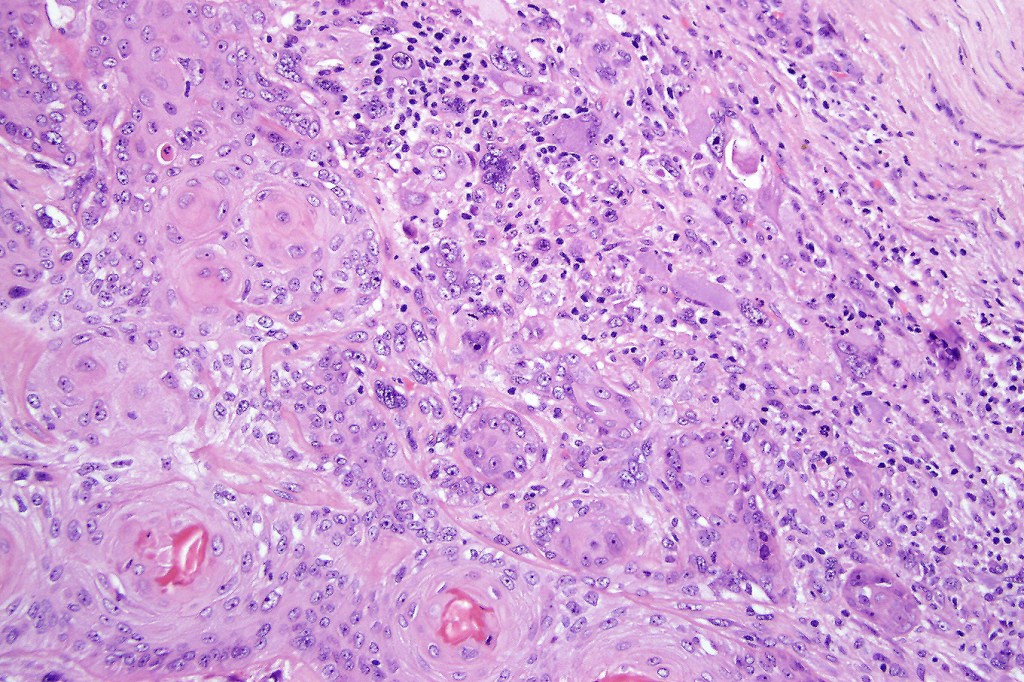

Carcinosarcoma

Cutaneous carcinosarcoma (metaplastic carcinoma, carcinoma with heterologous differentiation)

Histological features

•Osteoid

•Chondroid

•Smooth muscle

•MFH-like features with osteoclasts

•Neural differentiation